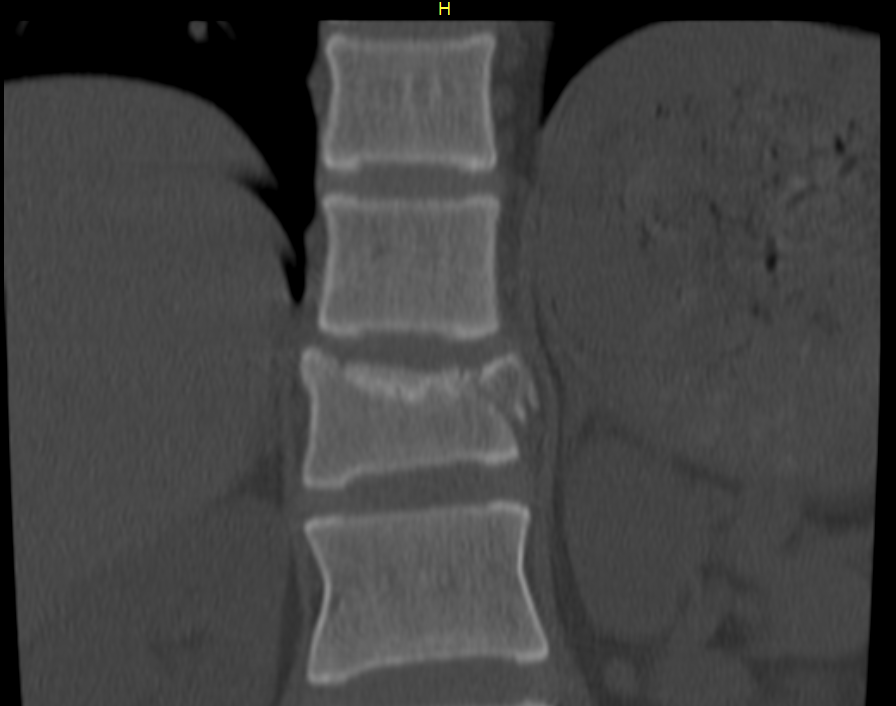

사례자분은 스노보드를 이용하다가 넘어지면서 엉치부터 바닥에 충격하셨고

이로 인한 충격으로 흉추 12번의 폐쇄성 압박골절 및 천추골절이 발생했습니다.

리고 천추골절로 요추 및 천추의 신경근이 손상됐구요.

2. 척추 압박률 확인

다행히 수술할 정도가 아니라면 척추압박률을 확인해야 하는데요.

압박률은 골절된 척추를 기준으로 윗 척추의 길이와 아래척추의 길이를 구해서 평균을 낸 후

골절된 척추의 길이로 나누면 산출되는데

사진에서 보는 것처럼 척추는 사다리꼴 형태로 눌리기 때문에

어느 지점에서 길이를 재느냐에 따라 압박률이 달라집니다.